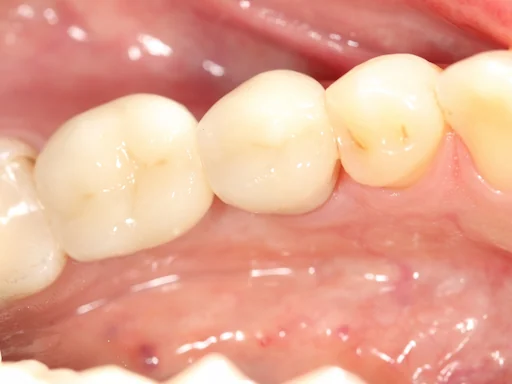

Patientenfall - Implantologie - Zahn 46 - 1

Schritt 1

Es handelt sich um einen eher ungewöhnlichen Fall, bei dem der Molar 4,6 in einer anderen Praxis bereits mehrfach chirurgisch vorbehandelt wurde. Der Zahn hatte eine erfolglose Wurzelkanalbehandlung erhalten. Danach wurde zweimal eine Wurzelspitzenresektion durchgeführt. Beide Wurzelspitzenresektionen waren ebenfalls erfolglos. Es traten immer wieder Fistelgänge auf. Es bildete sich eine große Zyste, die sich bereits in Richtung Nervenkanal ausdehnte.